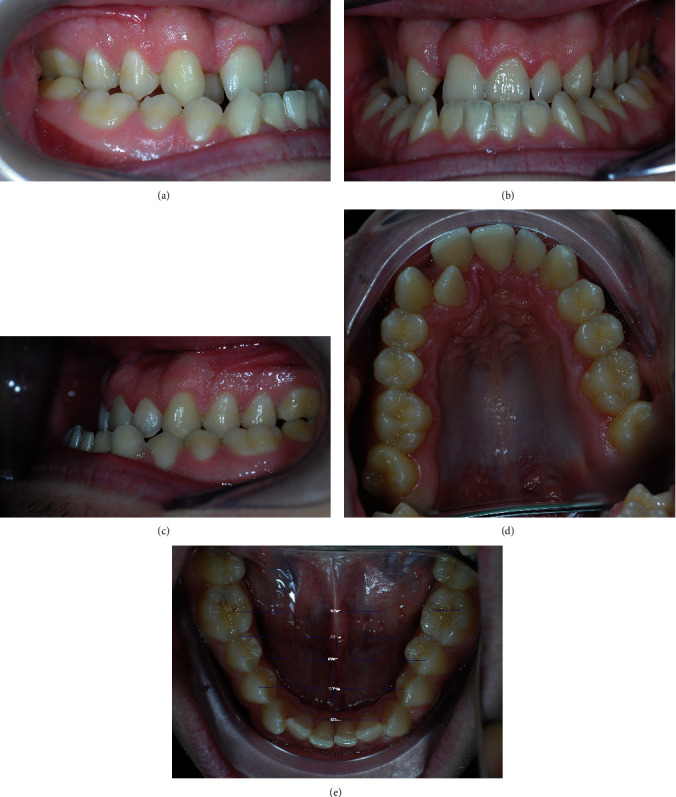

在本病例报告中,我们介绍并讨论了一名17岁男性患者的正畸/正颌联合治疗骨骼错颌矫正的数字工作流程,该患者患有骨骼III类,面部不对称,颅骨中三分之一矢状和横向缺陷,牙齿拥挤和双侧交叉咬合。第一阶段的治疗包括手术辅助快速腭扩张和咬合失代偿,使用固定的自结扎器。使用正畸软件包(即Dolphin 3D Surgery模块)通过整合锥束计算机断层扫描采集、口内扫描和口外照片的数据进行虚拟治疗客观评估。该软件可以对骨骼、牙槽牙和软组织的不和谐进行综合评估,根据骨骼和美学目标对手术过程进行定性和定量模拟,从而对错牙合进行治疗。利用该软件的特定功能,根据预先编程的骨骼运动设计手术夹板,随后使用三维(3D)打印技术生成物理夹板。一旦达到适当的咬合失代偿,就进行上颌骨的Le Fort I截骨术和双侧下颌矢状面手术截骨术以恢复适当的骨骼关系。治疗时间8个月。正畸/正颌联合治疗可以纠正骨骼和牙齿的不平衡,改善面部美观。因此,在虚拟环境中计划的治疗目标得以实现。虚拟规划为在单个虚拟3D模型中可视化牙弓与周围骨骼和软结构之间的关系提供了新的可能性,允许专家模拟不同的手术和正畸手术,以实现患者的最佳结果,并在治疗具有挑战性的错颌时提供准确和可预测的结果。

In the present case report, we present and discuss the digital workflow involved in the orthodontic/orthognathic combined treatment of a skeletal malocclusion correction in a 17-year-old male patient affected by a skeletal class III, facial asymmetry, sagittal and transversal deficiency of the medium third of the skull, dental crowding, and bilateral cross-bite. The first stage of the treatment involved surgically assisted rapid palatal expansion and occlusal decompensation, using fixed self-ligating appliance. An orthodontic software package (i.e., Dolphin 3D Surgery module) was used to perform virtual treatment objective evaluation by integrating data from cone beam computer tomography acquisition, intraoral scan, and extraoral photographs. The software allowed a comprehensive evaluation of skeletal, dento-alveolar, and soft-tissue disharmonies, qualitative and quantitative simulation of surgical procedure according to skeletal and aesthetic objectives, and, consequently, the treatment of the malocclusion. Using a specific function of the software, the surgical splint was designed according to the pre-programmed skeletal movements, and subsequently, the physical splint was generated with a three-dimensional (3D) printing technology. Once a proper occlusal decompensation was reached, a Le Fort I osteotomy of the maxilla and a bilateral sagittal surgical osteotomy of the mandible were executed to restore proper skeletal relations. The whole treatment time was 8 months. The orthodontic/orthognathic combined treatment allowed to correct the skeletal and the dental imbalance, as well as the improvement of facial aesthetics. Accordingly, the treatment objectives planned in the virtual environment were achieved. Virtual planning offers new possibilities for visualizing the relationship between dental arches and surrounding bone and soft structures in a single virtual 3D model, allowing the specialists to simulate different surgical and orthodontic procedures to achieve the best possible result for the patient and providing an accurate and predictable outcome in the treatment of challenging malocclusions.